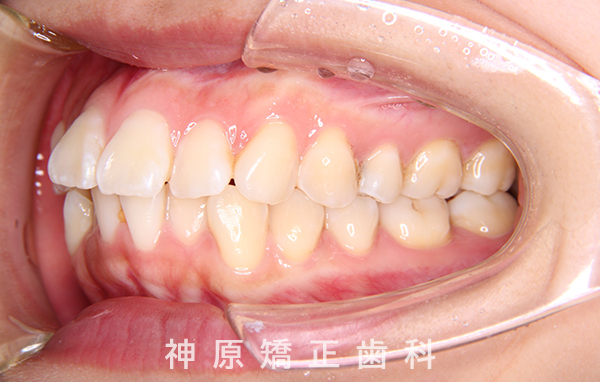

初診時

口元の突出感と下の歯並びの乱れを改善するため、小臼歯を抜歯することにしました。抜いたスペースを利用して、前歯をできるだけ後ろに移動させるため、上下に歯科矯正用アンカースクリューを使用する計画を立てました。治療の目標について同意を得た後、矯正治療を開始しました。歯の動きが順調で、1年9カ月で治療が完了しました。その結果、側貌はE-lineに調和したバランスの良い仕上がりになりました。